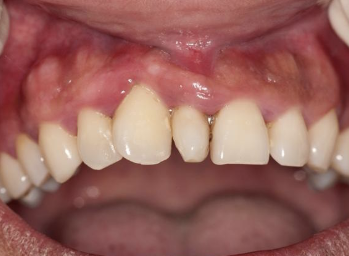

AD, AR, X-linked; both deciduous and permanent dentition are diffusely involved, affects enamel (soft, thin, easily damaged, susceptible to decay), dentin is exposed

amelogenesis imperfecta (AI)

Clinical appearance of AI

yellow-brown to white pitted lesions, open bite, loss of contact